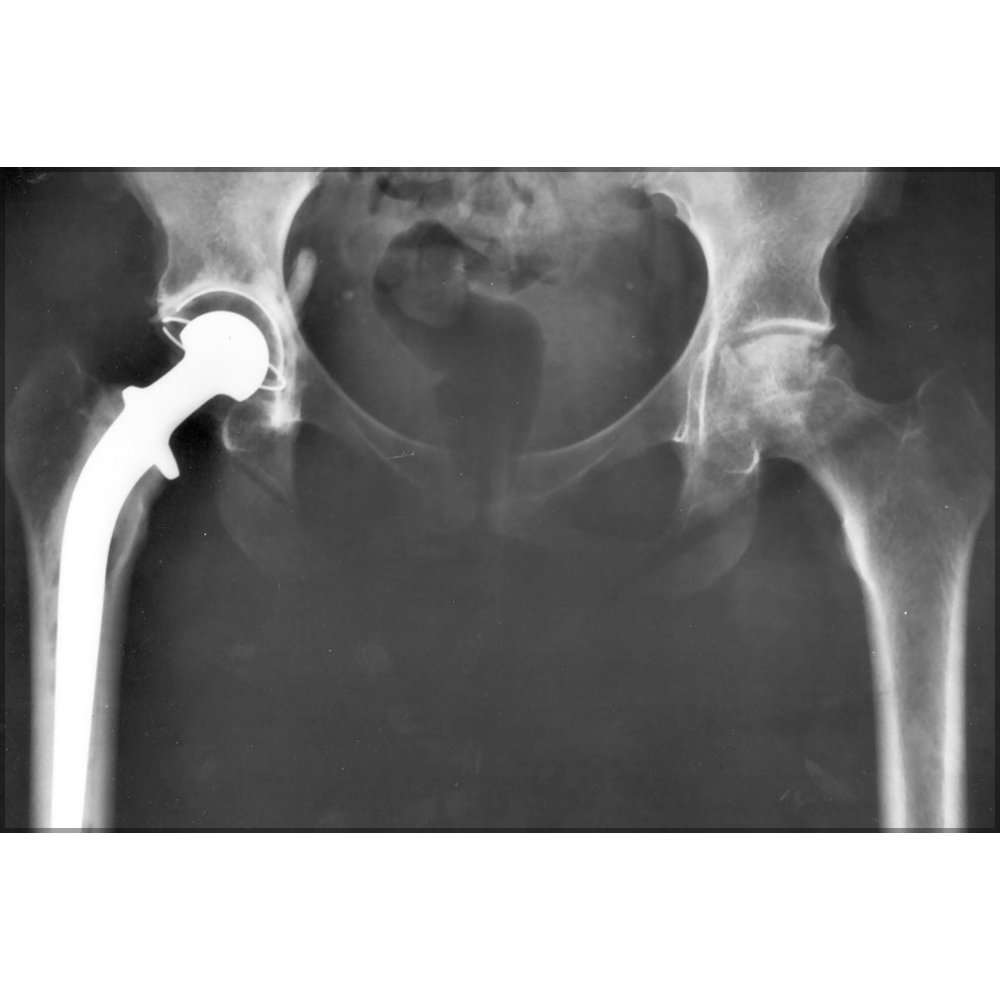

Person with an artificial hip, Xray Stock Image F029/8972 Can An Artificial Hip Pop Out  Symptoms of a loose hip replacement include pain in the groin or upper thigh, new popping or clicking noises, joint instability, and dislocation or subluxation (partial dislocation The risk is greatest in the first months after surgery. Patients undergoing hip arthroplasties should The problem usually starts with a popping or slipping sensation. If you bend in the wrong way or. Can An Artificial Hip Pop Out.